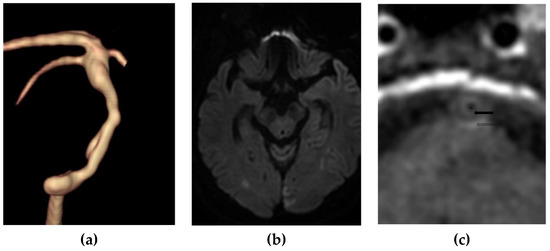

Figure 1.

A 78-year-old man with embolic infarction of both occipital lobes. (a) Volume rendering imaging using Time-of-Flight MR angiography showed a diffuse atherosclerotic narrowing of the basilar artery. The maximal wall thickness is 3.8 mm and the stenosis degree is 67%. (b) Diffusion-weighted imaging showed diffusion restriction in both occipital lobes. (c) Contrast-enhanced T1-weighted imaging showed a layered finding between an enhanced fibrous cap (arrow) and adventitia (open arrow) and an intervening nonenhanced lipid-rich necrotic core. * represents the lumen.

Ninety-five patients with a atherosclerotic plaque in the BA were included in our study. The demographic data and plaque characteristics of patients are described in Table 1 and Table 2. Of these patients, 43 (45.3%) had positive findings on DWI. Ten (10.5%) cases were identified as having a layered plaque with an LRNC on CE-T1W BB imaging. Of these patients, 9 had positive findings on DWI (Figure 1). The prevalence of a layered plaque with an LRNC on CE-T1W BB imaging was significantly higher than that on DWI (90.0% vs. 43.5%, p = 0.016). The extent of stenosis in patients with an LRNC on CE-T1W BB imaging was significantly greater than that of patients without an LRNC (p < 0.001). The maximum wall thickness in patients with an LRNC on CE-T1W BB imaging was significantly greater than that of patients without an LRNC (p = 0.008).

In our study, 10 (10.5%) patients were identified as having a layered plaque by an enhanced fibrous cap and adventitia and a nonenhanced LRNC on CE-T1W BB imaging. Of these patients, 9 were symptomatic. Layered plaques that were visualized on CE-T1W BB imaging showed a BA plaque with thick walls and high-grade stenosis. These findings suggest that VW-MRI in patients with a large plaque volume in the BA can show a layered plaque.